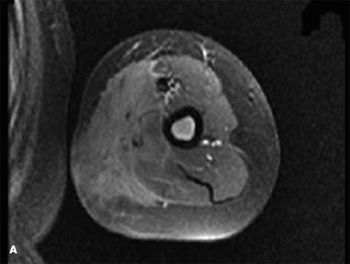

For 3 months, a 9-year-old boy had swelling of the left upper arm. An MRI scan obtained at another facility 1 week after onset showed extensive edema of the soft tissue at the midhumeral level. Laboratory results, including complete blood cell (CBC) count and Lyme titer, were normal.